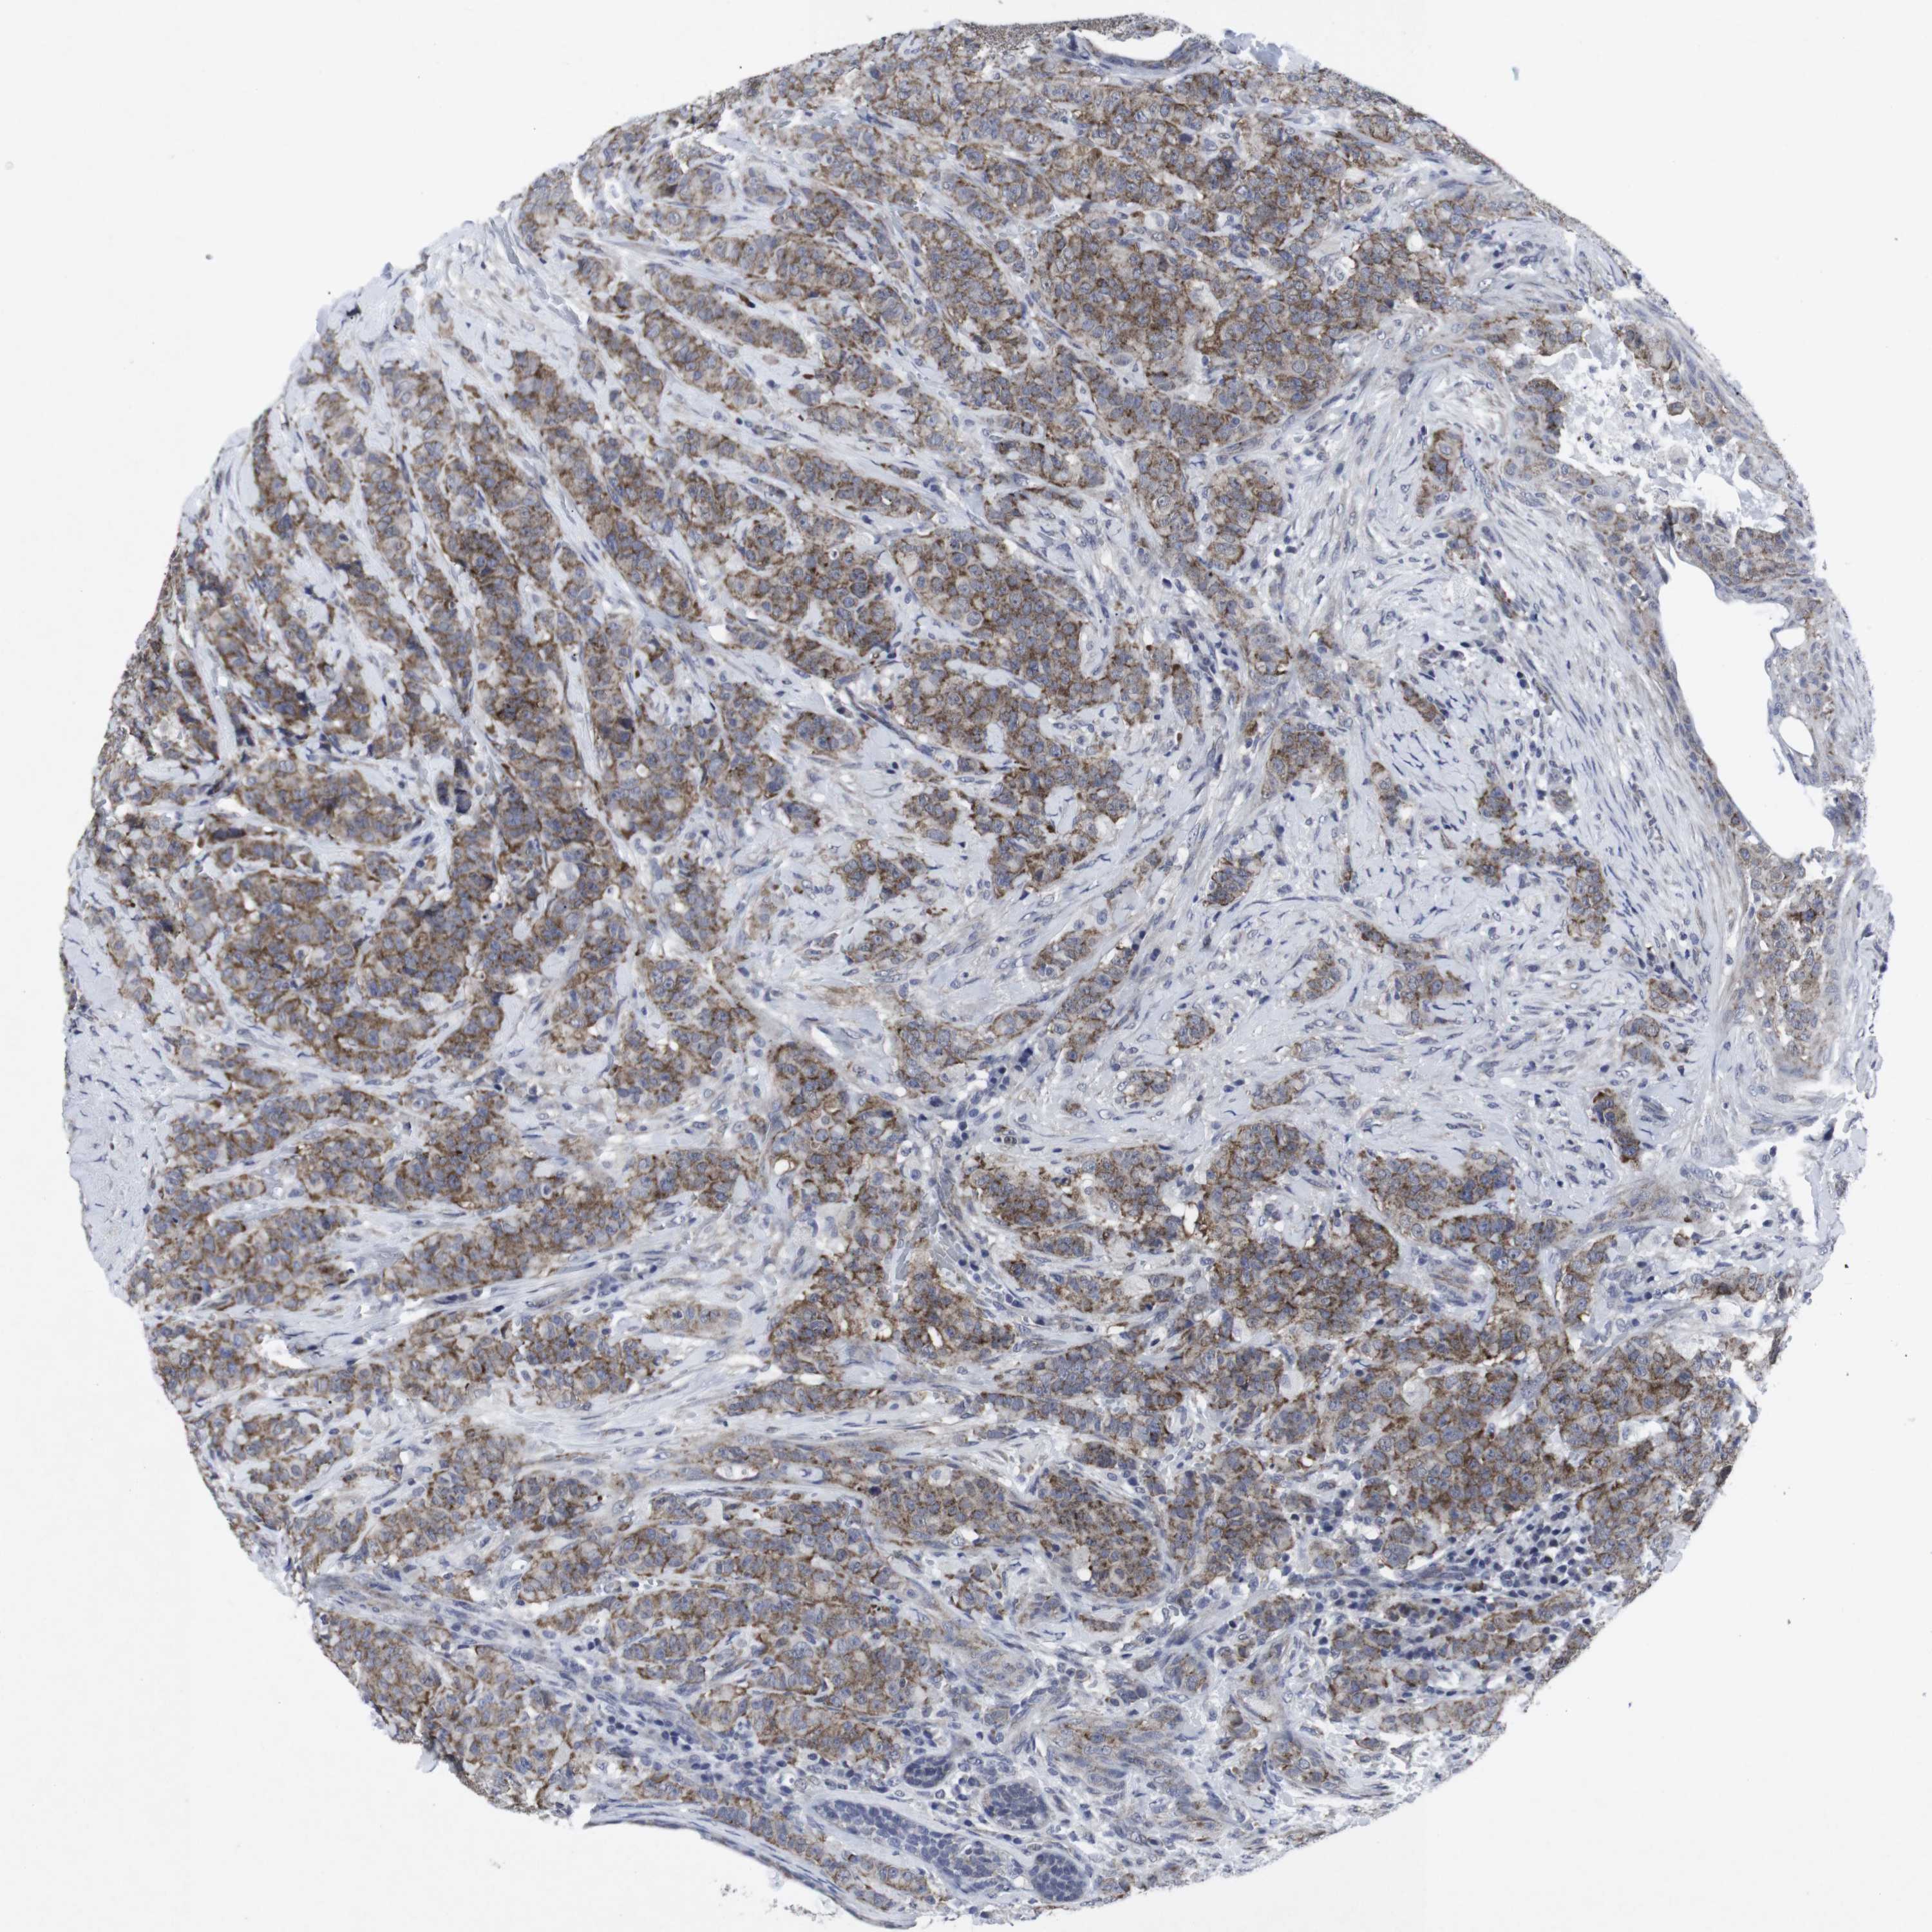

CANCER BREAST CANCER Show tissue menu

BRCA TCGA BRCA VALIDATION PROTEIN EXPRESSION

ANTIBODIES

AND

VALIDATION